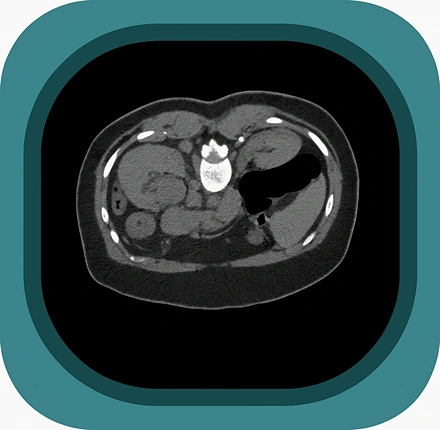

Explore full-body CT anatomy in 3 planes. Our high-resolution, carefully labelled images reveal micro-anatomy—ideal for radiologists, radiographers and surgeons.